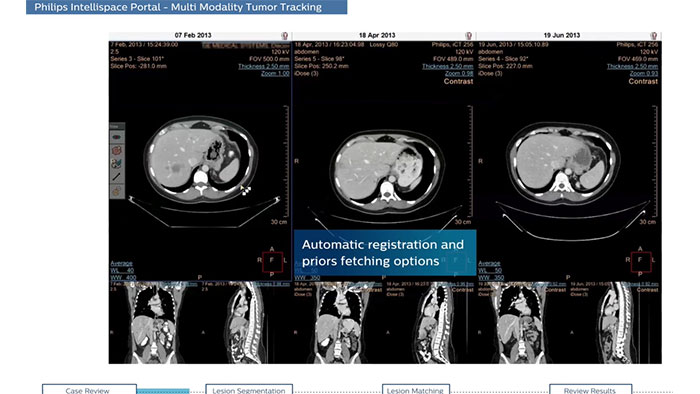

Streamlined workflow for follow up and analysis of oncology patients

MMTT is a post processing software used to display, process, analyze and quantify anatomical and functional images, for CT, MR, PET/CT, SPECT/CT and Dual Energy CT at one or multiple time points.

Benefits